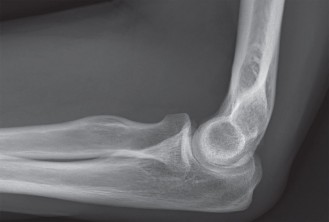

A 43-year-old, active man presents to your clinic with a chief complaint of elbow pain. He tells you that he …